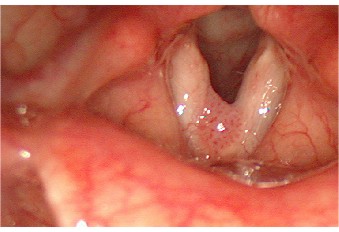

Telenagiektični polip slobodnog ruba glasnice. Pojačan crtež krvnih žila glasnica

Polipi grkljana u pravilu su  smješteni na glasnicama i najčešće su benigne izrasline u tom organu. Najčešće su smješteni na granici prednje i srednje trećine glasnica i to na njihovu slobodnu rubu, što ukazuje na njihov najvjerojatniji mehanizam nastanka a to je fonotrauma - mehaničko oštećenje glasnica tijekom fonacije. Polipi, ipak, mogu biti smješteni i na drugim dijelovima glasnica, a mogu nastati i kao posljedica oštećenja tkiva tijekom  jakog kašlja. Oni su najčešće crveno obojeni jer su građeni od proširenih krvnih žila, ali mogu biti bijeli – fibrozirani ili prozirni. Polipe na glasnicama češće dobivaju pušači i osobe koje ekscesivno upotrebljavaju svoj glas. Također je veća  vjerojatnost razvoja polipa kod akutnog ili kroničnog laringitisa povezanog s hiperemijom glasnica, te se smatra da fonotrauma ili kašalj dovode do distenzije sluznice i uraštanja već proširenih krvnih žila u polip, zbog čega su laringealni polipi najčešće tzv.  teleangiektatični noduli – dakle građeni od proširenih krvnih žila. Polipi glasnica u pravilu dovode do promuklosti, ali promuklost je najjače izražene kod polipa slobodnog ruba i kod velikih polipa koji ometaju fonacijsko približavanje glasnica. Ne postoji tipična promuklost za polip, pa se prema tome dijagnoza postavlja pregledom larinksa. Liječenje polipa je kirurško u tehnici laringomikroskopije slijedeći principe fonokirurgije tj. maksimalnog čuvanja sluznice glasnica i slobodnog ruba glasnica. Ako postoje tzv. varikoziteti glasnica, pri operaciji polipa poželjno ih je koagulirati laserom. Svaki polip treba i histološki analizirati, jer se ponekad, posebice u starijih osoba, može raditi o polipoidnoj formi karcinoma glasnica. Kako ne bi recidivirali, treba bolesniku savjetovati prestanak pušenja, saniranje upalnih promjena u larinksu, izbjegavanje fonotraume, a ponekad treba primijeniti i postoperacijsku glasovnu terapiju i edukaciju.